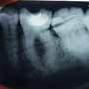

Fase diagnostica, che prevede una prima anamnesi clinica, una radiografia pre-operatoria per interpretare l’anatomia endodontica, al fine di definire un corretto piano di trattamento.

La diagnosi in endodonzia non può prescindere dall’esecuzione di esami radiologici accurati, in grado di mostrare l’esatta anatomia delle strutture dentali, in particolare dell’anatomia radicolare e dei tessuti di supporto.

Le apparecchiature radiologiche convenzionali (endorali) forniscono una rappresentazione bidimensionale di strutture anatomiche tridimensionali.

Questa immagine “appiattita” può nascondere, sovrapponendole, alcune aree anatomiche, soprattutto quelle in senso bucco-vestibolare (spessore dei tessuti).

Anche adottando tecniche radiografiche in grado di migliorare la qualità dell’immagine (tecnica del cono lungo con centratore “tipo Rinn”, proiezione dei raggi con inclinazione mesio-distale), i limiti tecnologici imposti dagli apparecchi endorali non sempre sono superabili.